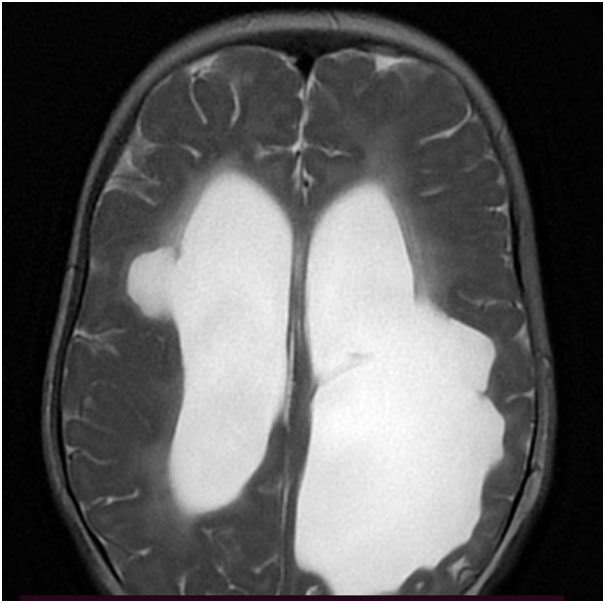

Hence, the first step in the diagnostic process is getting an MRI of the brain done. Neuroimaging in this patient (Figure 1 A-B) suggested a structural etiology (Porencephalic cysts).

In the absence of an apparent acquired etiology (uneventful pregnancy and perinatal period), inherited causes were considered. The imaging features (porencephalic cysts with microhemorrhages) pointed to a possibility of COL4A1-related disorder. Exome sequencing showed a heterozygous missense variation (pathogenic) in exon 45 of COL4A1 gene confirming the diagnosis. Parents tested negative for this variant.

Presence of porencephalic cysts with microhemorrhages in deep gray matter and periventricular and subcortical white matter, are the hallmark radiological features. Other imaging findings include diffuse periventricular leukoencephalopathy, lacunar infarcts, and dilated perivascular spaces.

Figure 1B:

SWI images – blooming along the bilateral ventricular lining indicating hemorrhagic residue